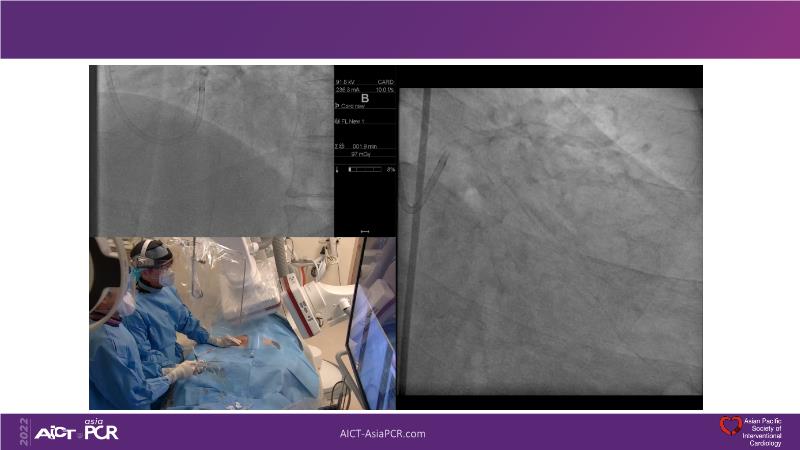

Beginning with the end in mind - FFR vs. IVUS imaging

Consult this session if you want to explore different plaque modification techniques and technology and see how to maximise PCI outcome with IVUS imaging. Also assess when to select FFR to determine when to treat vs. IVUS to determine where and how to treat.

- To explore different plaque modification techniques and technology

- To maximise PCI outcome with IVUS imaging

- To leverage FFR to determine when to treat vs. IVUS to determine where and how to treat